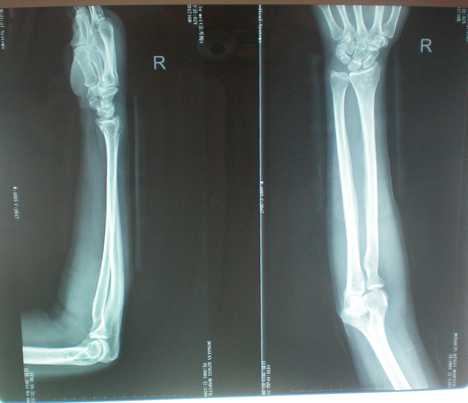

手法正骨后...

手法正骨前

余**,女,55岁

患者不慎摔倒损伤右手,后经拍片示:右桡骨粉碎性骨折伴右桡尺关节半脱位,医院建议手术治疗,患者不想手术,想中医保守冶疗,后经朋友介绍来诊,经本门诊特色手法整骨及夹板固定,再次拍片示,骨折对位对线良好已达98%以上。